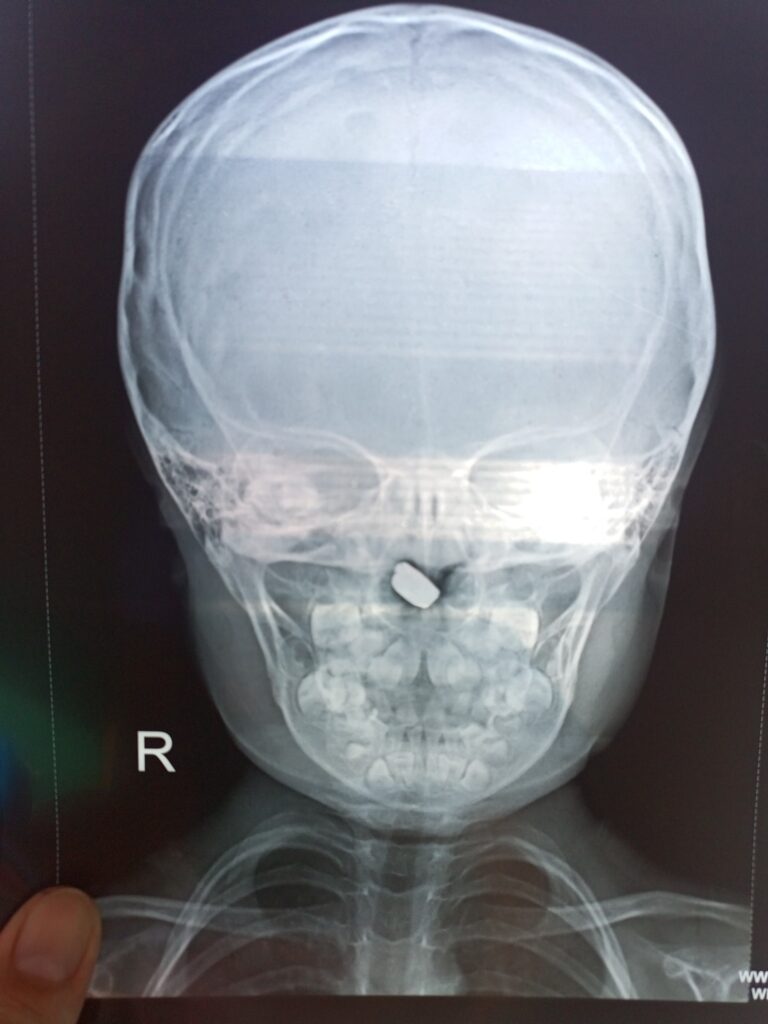

ວັນທີ 7 ທັນວາ 2025 ທ່ານ ກິ່ງແກ້ວ ອິນທະວົງ ໝໍປະຈຳຫ້ອງການສາທາລະນະສຸກ-ໂຮງໝໍເມືອງຄຳເກີດ ແຂວງບໍລິຄຳໄຊ ໄດ້ໂພສເລົ່າເຫດການວ່າ: ແມ່ຂອງເດັກເພດຍິງ ອາຍຸ 5 ປີ ຢູ່ບ້ານນາເຄືອ ເມືອງປາກກະດິງ ໄດ້ພາລູກມາກວດຍ້ອນລູກສາວມີອາການນ້ຳມູກຍ້ອຍເບື້ອງໜຶ່ງ ແລະ ມີກິ່ນ ແມ່ເດັກແຈ້ງວ່າເປັນແບບນີ້ມາໄດ້ 6 ມື້ແລ້ວ.

ຜົນການກວດກາພົບເຫັນຖ່ານໂມງຄາຢູ່ໂກບດັງ ແລະ ຕິດແໜ້ນ ຈຶ່ງໄດ້ຮີບຮ້ອນຊ່ວຍເອົາຖ່ານໂມງອອກໃຫ້ເດັກ ໄດ້ຢ່າງປອດໄພ.